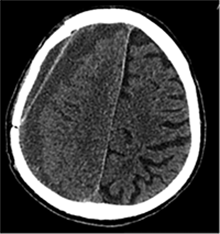

53 m. vyras sumuštas gatvėje ir greitosios medicinos pagalbos atvežtas į Priėmimo skyrių. Pacientui atlikta galvos kompiuterinė tomografija (GKT). Rasta: poūmė, stora, apie 16 mm dydžio subdurinė hematoma (SDH) dešinėje pusėje konveksitaliai ir ūmi nedidelė SDH kairėje pusėje frontoparietaliai. Vidurio struktūrų dislokacija (VSD) į kairę – minimali. Kairėje – kaukolės skliauto linijinis lūžis. Nustatyta nosies kaulų, nosies pertvaros, dešiniojo viršutinio žandikaulio kaktinės ataugos ir kūno, sinuso sienelių lūžių, dešinės akiduobės medialinio krašto lūžių ir dešiniojo skruostinio lanko lūžių (1 pav.). 2020 m. liepos mėn. pacientas skubos tvarka operuotas: atlikta dešinė kraniotomija, pašalinta hematoma. Atlikus kontrolinę GKT, buvo matyti, kad pašalinta didžioji hematomos dalis (2 pav.). Pacientas konsultuotas veido ir žandikaulio chirurgo, skubus chirurginis gydymas neindikuotas. Praėjus 3 savaitėms, pacientas, esant gerai funkcinei ir neurologinei būklei, tolesnio gydymo perkeltas į slaugos ligoninę, vėliau išleistas gydytis ambulatoriškai.

1 pav. Prieš pirmąją operaciją (poūmė, stambi, iki 16 mm SDH apie dešinįjį pusrutulį, ūmi nedidelė SDH kairėje F-P; VSD į kairę ~3 mm)